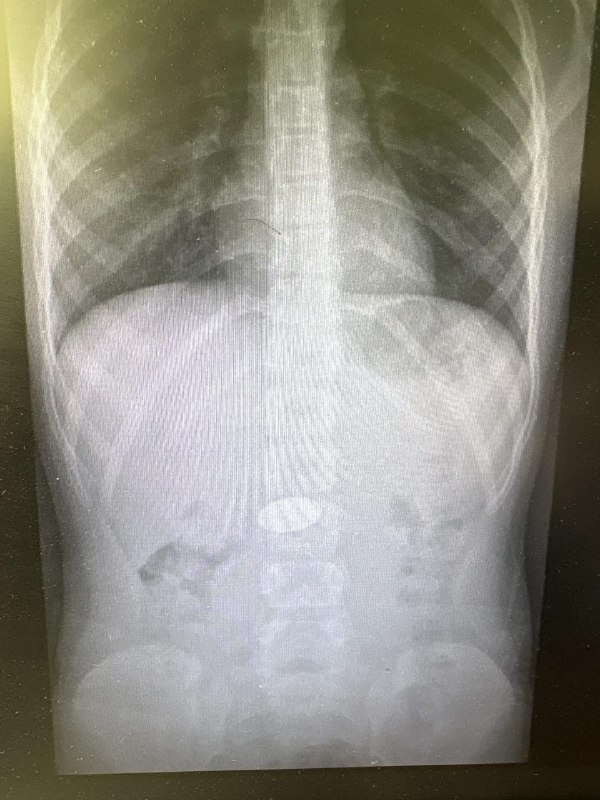

В детское хирургическое отделение клинической больницы №7 поступил маленький ребенок. Врачи обнаружили в его желудке крупную 5-рублевую монету, которую малыш проглотил из-за недосмотра родителей. Благодаря профессионализму медиков, инородное тело было успешно извлечено. Сейчас ребенок выписан и находится дома.

Фото: Комитет здравоохранения Волгоградской области